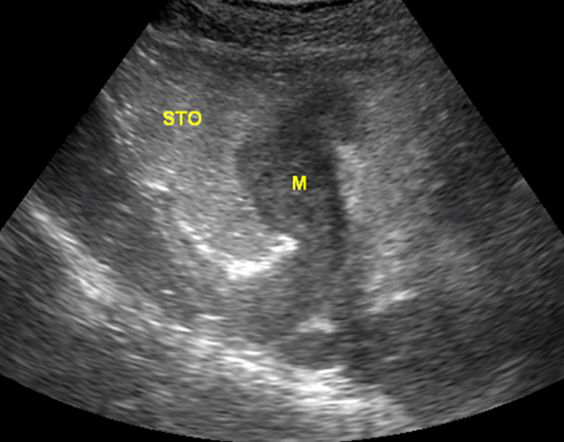

胃间质瘤

胃造影用的是什么机子超声诊断科新技术|胃肠超声造影检查,让您舒舒服服做完肠胃筛查!_https://www.jmylbn.com_新闻资讯_第8张